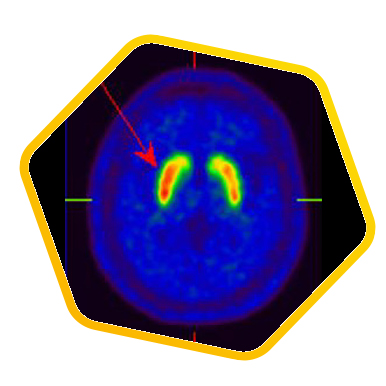

![]() [C-11] Raclopride |

![]() [F-18] DOPA |